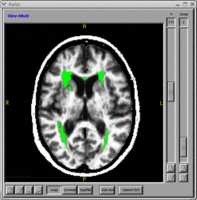

- BRAINSTracer - Tracing tool that uses thge vtkContourWidget for defining a region of interest manually. NITRC Link